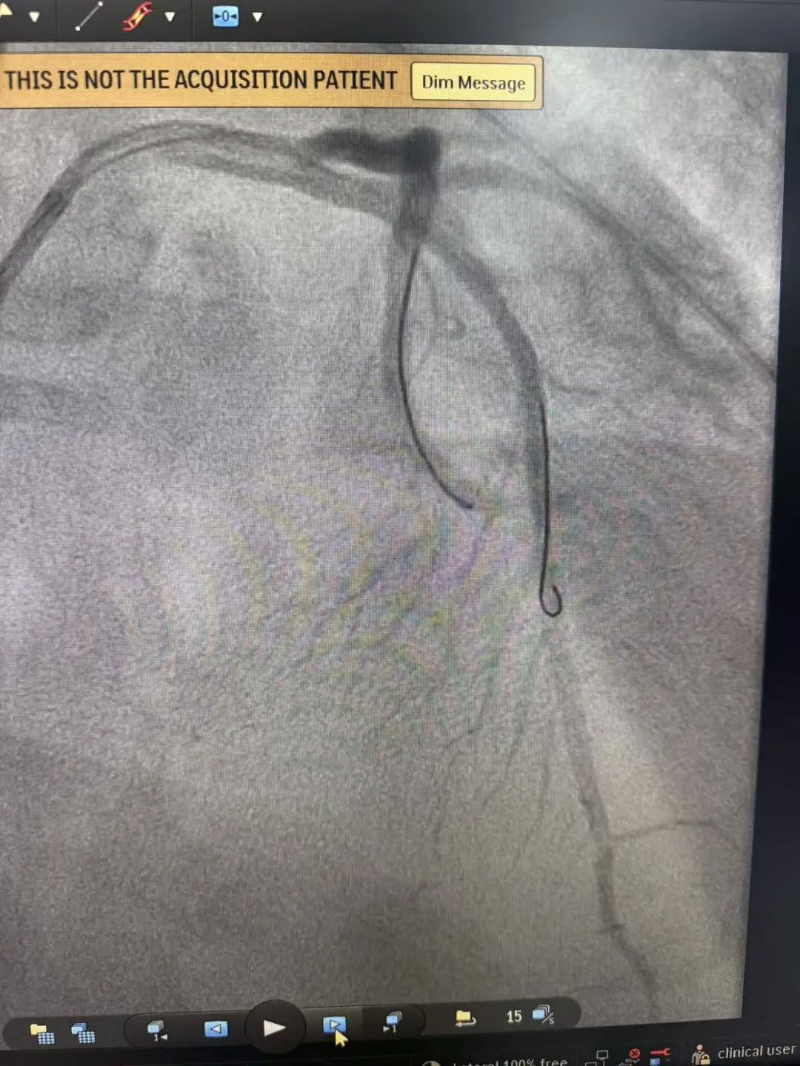

心脏恢复跳动意味着有了手术机会,患者被迅速送入介入室。介入室技师和护士早已准备就绪,惠州市中心人民医院中文博彩平台分院麻醉科医生也已到位。手术由温灵武和文轶医生共同完成。造影显示,患者前降支开口处完全闭塞,医生迅速开通闭塞血管并植入支架一枚,术后血流恢复良好。从患者进入介入室到血管开通,仅用时20余分钟。

造影见前降支

开口就完全闭塞

手术后血流恢复